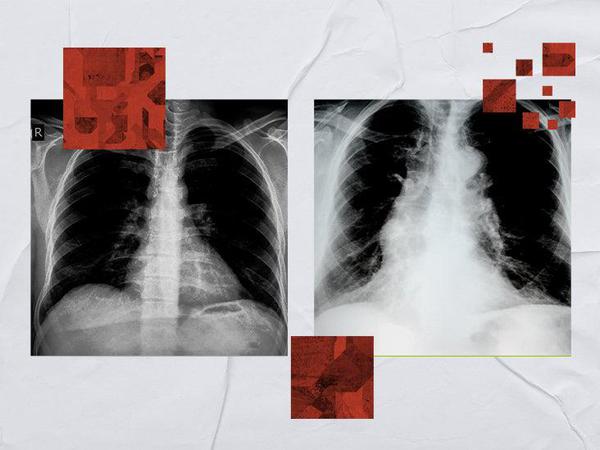

COPD lung vs. normal lungs: What COPD looks like

COPD may not always show up on an X-ray. However, when it does, doctors may notice visible signs, such as air pockets in lung tissue, a lowered diaphragm, or enlarged lungs. Chronic obstructive pulmonary disease (COPD) is a serious group of lung conditions that includes chronic bronchitis and emphysema. These conditions cause permanent changes in the lungs that make breathing more difficult. Doctors may opt to use CT or MRI scans instead of X-rays to get a clearer image of the inside of the lung